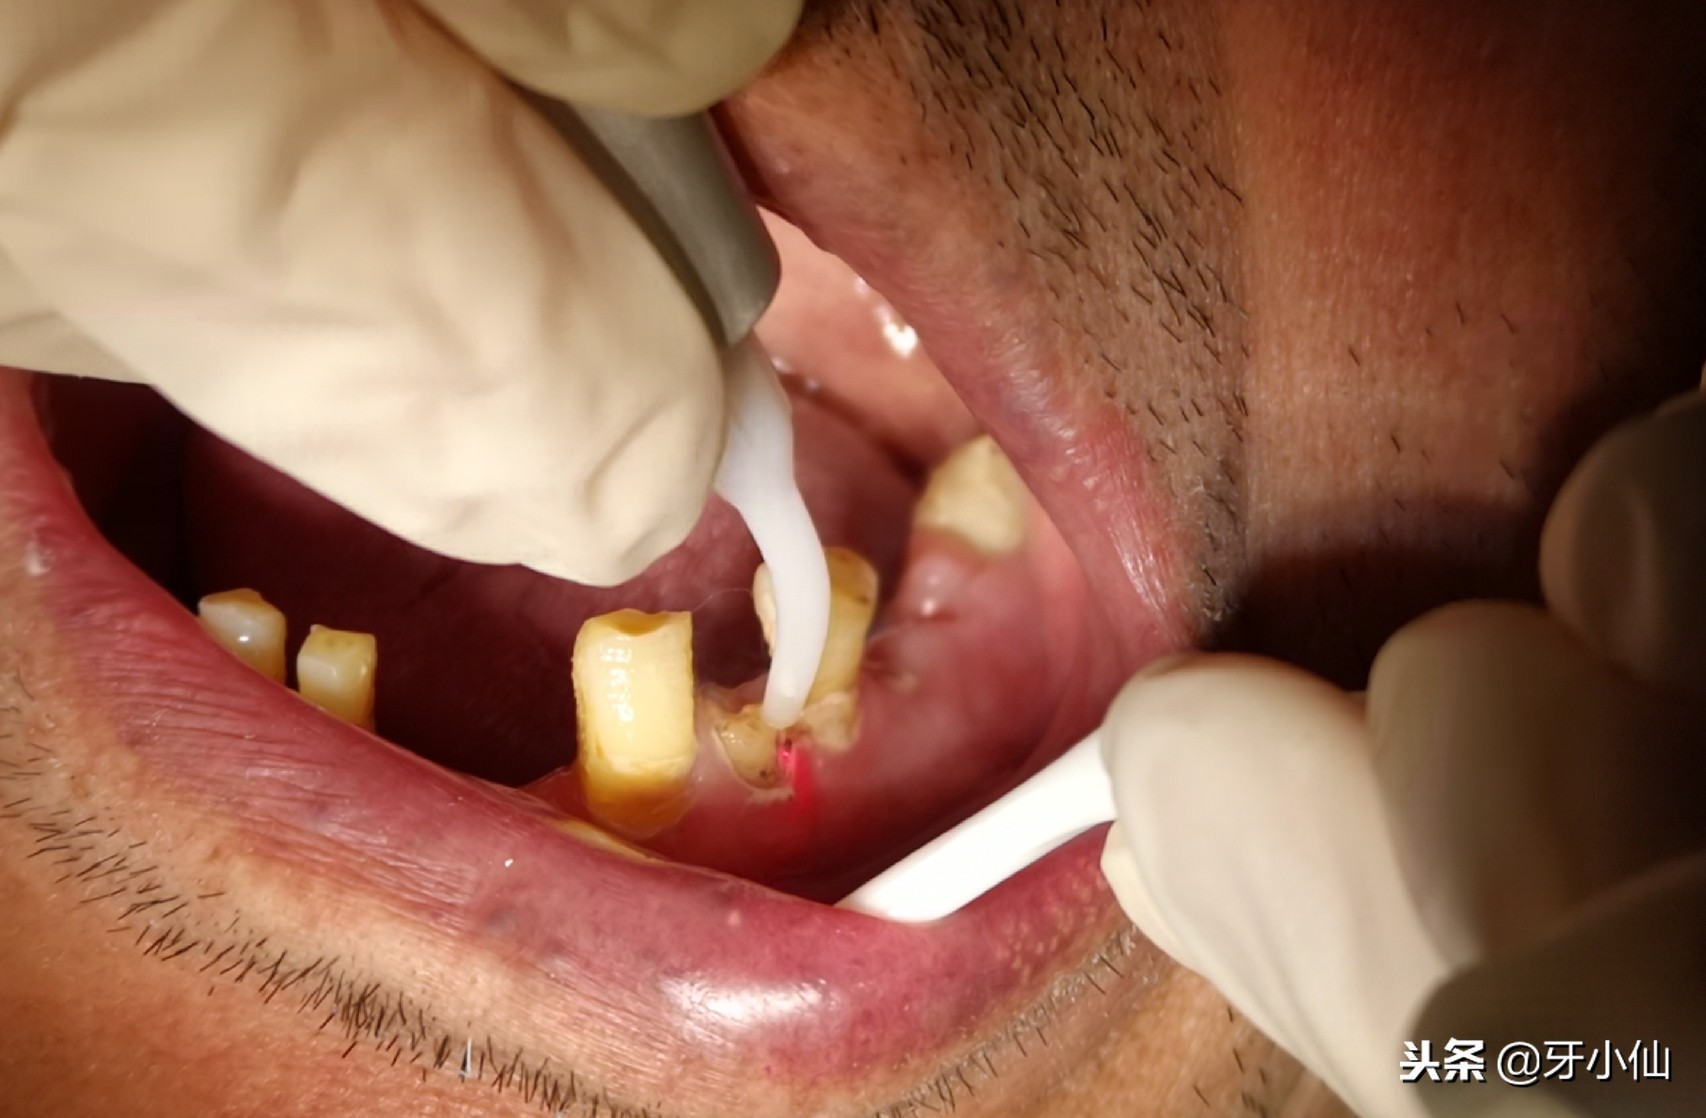

激光拔牙

如果是在设备齐全的口腔科拔牙,有无痛麻醉仪、超声骨刀、激光等先进设备帮助医生减少你的不适感哦。拔掉坏牙,去除隐患,有何不可呢?